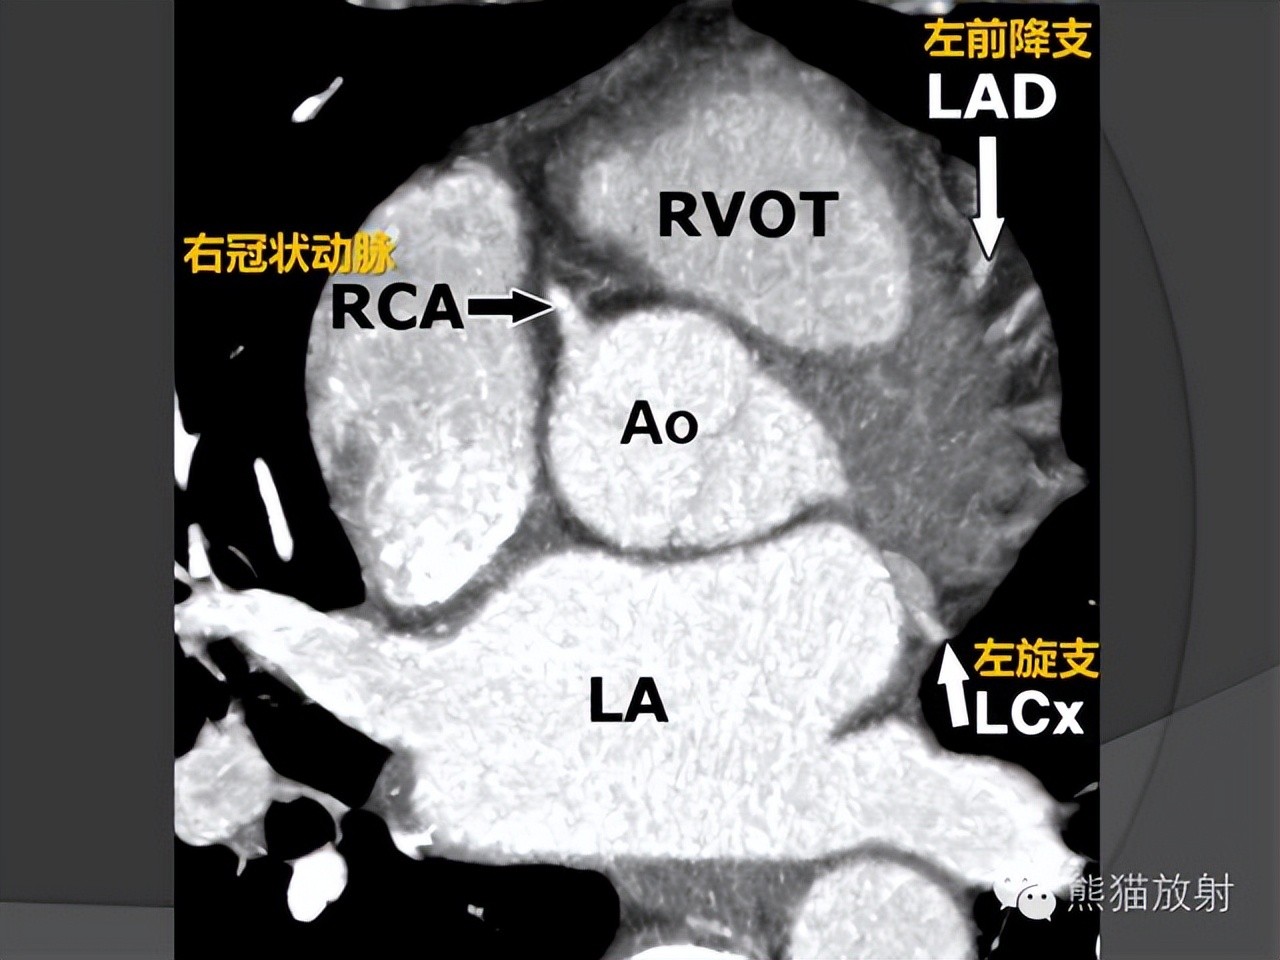

冠状动脉CTA解剖